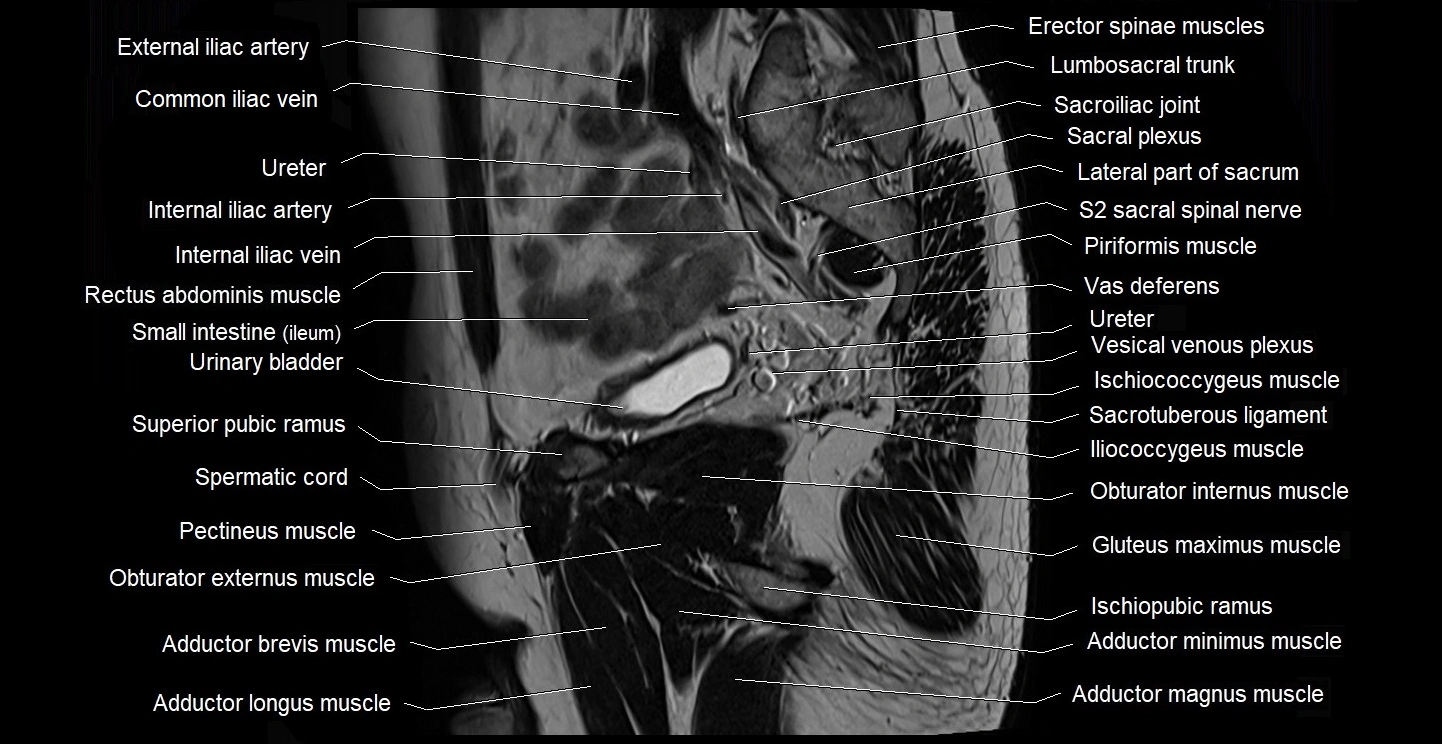

- Adductor brevis muscle

- Adductor longus muscle

- Adductor magnus muscle

- Adductor minimus muscle

- Erector spinae muscles

- Gluteus maximus muscle

- Gracilis muscle

- Iliococcygeus muscle

- Ischiopubic ramus

- Levator ani muscle

- Lumbosacral trunk

- Obturator externus muscle

- Obturator internus muscle

- Pectineus muscle

- Piriformis muscle

- Sacral plexus

- Sacroiliac joint

- Sacrotuberous ligament

- Sciatic nerve

- Seminal vesicle

- Spermatic cord

- Superior pubic ramus

- Vas deferens

- Vesical venous plexus